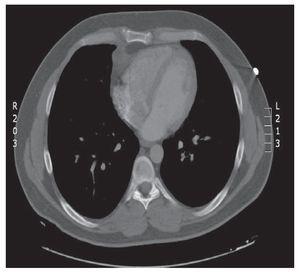

Necrosis de la grasa pericárdica

del Pozo Rivas, Villena Garrido, Benavides Mañas

Revista de Patología Respiratoria 2011;14:106-7

Acceso a texto completo